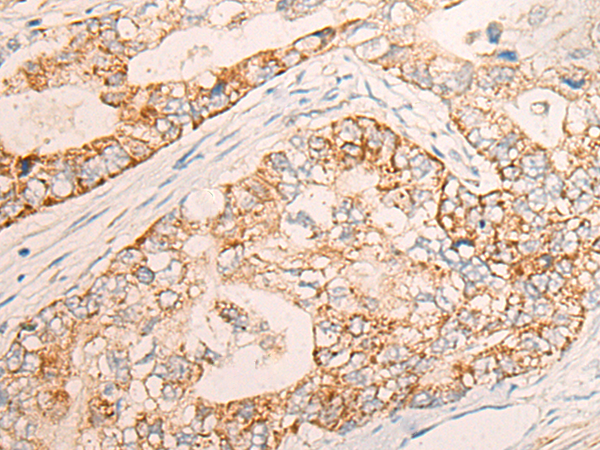

The image is immunohistochemistry of paraffin-embedded Human esophagus cancer tissue using 46965(COG2 Antibody) at dilution 1/30. (Original magnification: ?00)